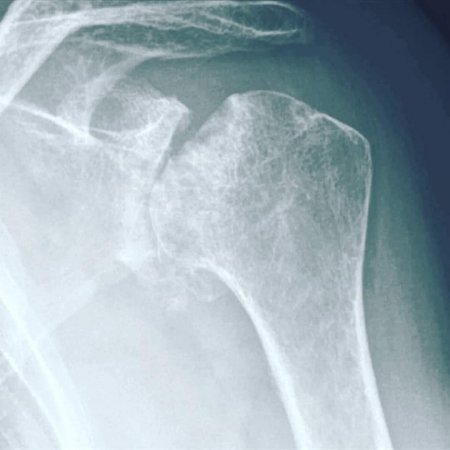

На цьому знімку плечового суглоба - деформація кісткової частини 4 ступіню. Зарадити нічим вже не можна. Не чекайте цього! Виправити, відновити, покращити функцію суглоба, хребта, враженого навантаженнями, чи віковими змінами, пов'язаними зі старінням - МОЖЛИВО! Гарна новина в тому, що Ви, при наявності будь-яких проблем с хребтом та суглобами, маєте змогу зараз, вчасно звернутись до лікаря-фахівця, який зупинить незворотні зміни. Запропонує метод відновлення, який, без перебільшення може врятувати Ваш хребет, чи суглоб, від заміни хірургом на штучний...